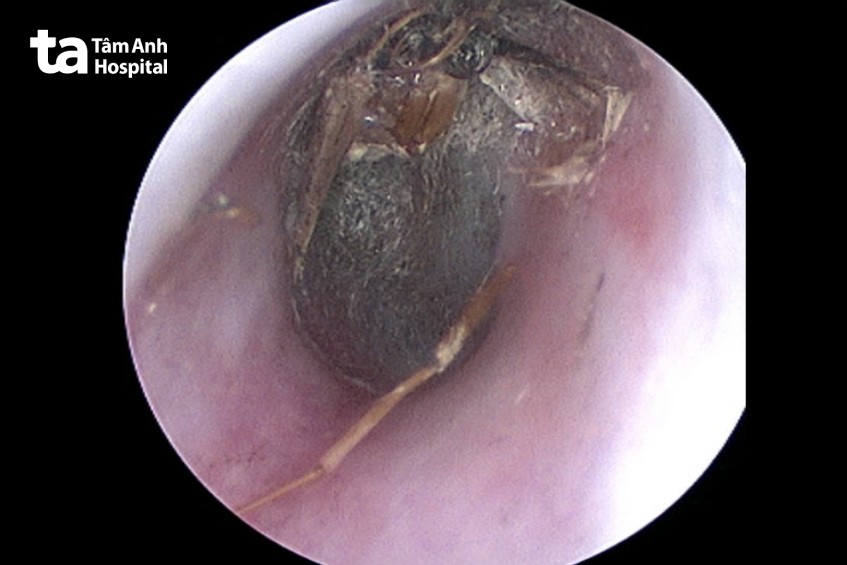

Thạc sĩ bác sĩ CKI Nguyễn Minh Tú, Trung tâm Tai Mũi Họng, Bệnh viện Đa khoa Tâm Anh TP.HCM nội soi tai người bệnh phát hiện con bướm đêm kích thước khoảng 2×3 cm, đã chết, dính vào ống tai trái tạo thành ổ viêm, sung huyết.

Bác sĩ Tú nội soi gắp con bướm đã chết ra khỏi tai bà P., vệ sinh tai, kê đơn thuốc điều trị, chẩn đoán dị vật ống tai trái, viêm ống tai, màng nhĩ nguyên vẹn.